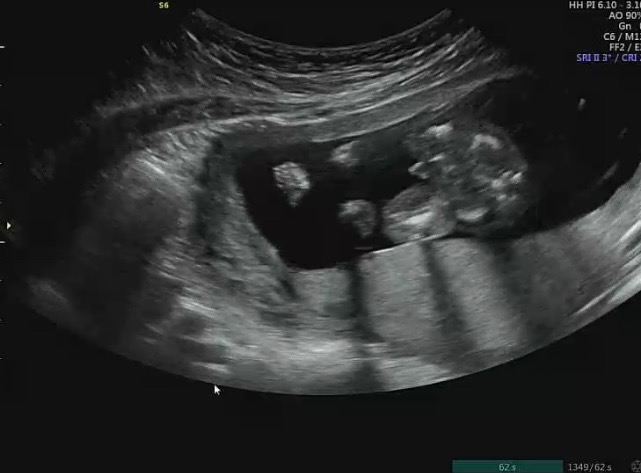

성별보러 병원다녀왔어요!

의사선생님은 애매하지만 딸 같다고 하셨는데 간호사선생님이 예약잡아주시면서 “저는 아들에 한표요..^^” 라고 하셔서 혼란스러워졌어요ㅠㅠ 제가 보기에도 딸 같긴한데.. 어떤 것 같은지 봐주세요!!!

네!! 다리사이에 쪼그만 삼각형!🌶️

주수에 따라 다를 듯 한데.. 14주 이상이면 아들이요! 저 자매맘..인데 그냥 매끈 그자체에요.. 삼각점 같기두 하구요

그렇군요..!! 주수는 16주에요!! 댓글 감사합니다 ㅎㅎ♥️